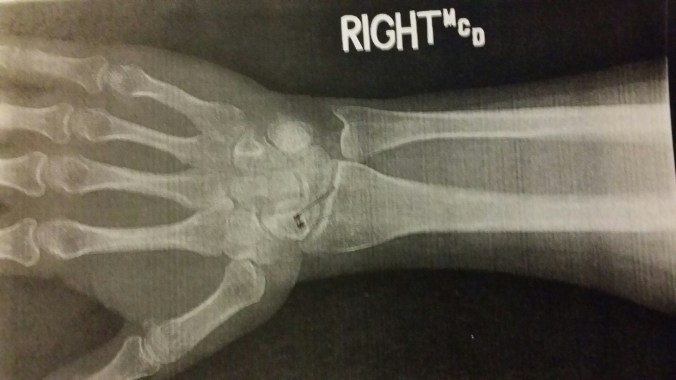

Jake thought these x-rays of my wrist and hand were awesome. He got to stand in the little radiology room and watch the tech take them. Neither of us were as impressed by the sound my apparently in stable bones made (think “click, click, CLICK!”) when the doctor was rotating my hand and wrist in various directions! It was really pretty freaky sounding!!!